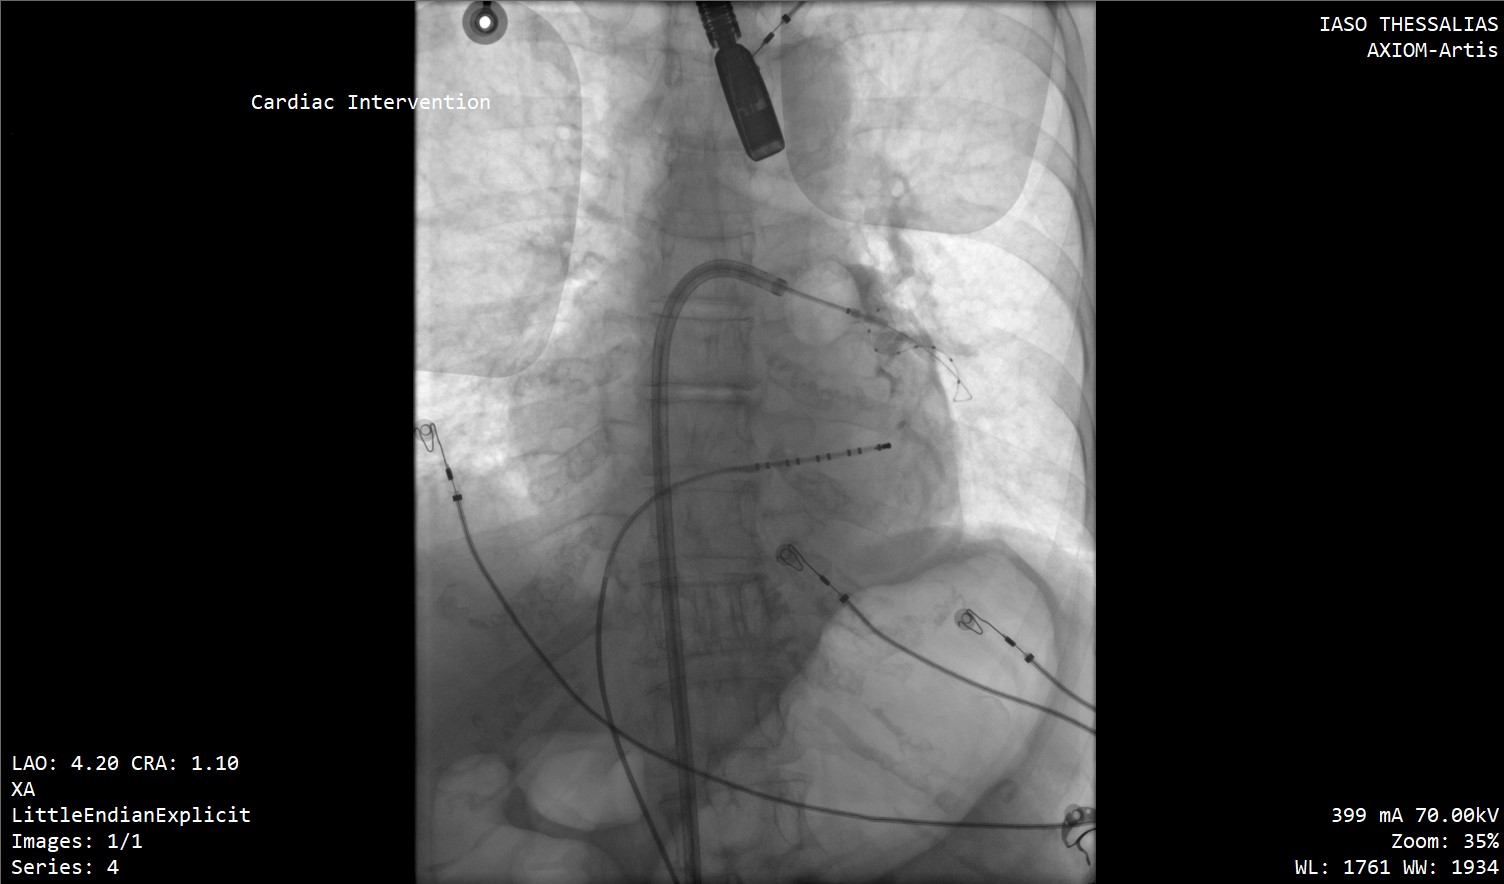

Μια νέα εποχή στην αντιμετώπιση των καρδιακών αρρυθμιών εγκαινιάζεται στην Κεντρική Ελλάδα, καθώς οι πρώτες επεμβάσεις κατάλυσης με καθετήρες (ablation) για τη θεραπεία της κολπικής μαρμαρυγής πραγματοποιήθηκαν με απόλυτη επιτυχία στο ΙΑΣΩ Θεσσαλίας.

Οι επεμβάσεις διενεργήθηκαν από τον Επεμβατικό Ηλεκτροφυσιολόγο Δημήτριο Α. Ιατρόπουλο, σε συνεργασία με τον Αναισθησιολόγο Δήμο Χαραλαμπίδη, τον Καρδιολόγο Αργύρη Γκαρμπούνη και την άρτια εκπαιδευμένη ομάδα του τεχνολογικού και νοσηλευτικού προσωπικού του Αιμοδυναμικού Εργαστηρίου του ΙΑΣΩ Θεσσαλίας.

Στις συγκεκριμένες επεμβάσεις εφαρμόστηκε η σύγχρονη τεχνική κρυοκατάλυσης με τη χρήση ειδικού μπαλονιού κρυοπηξίας (Cryoballoon), το οποίο επιτρέπει την ελεγχόμενη ψύξη («πάγωμα») του καρδιακού ιστού γύρω από τις πνευμονικές φλέβες, επιτυγχάνοντας με ασφάλεια και ακρίβεια την ηλεκτρική τους απομόνωση. Η μέθοδος χαρακτηρίζεται από υψηλά ποσοστά επιτυχίας, μειωμένο χρόνο επέμβασης και ταχεία ανάρρωση των ασθενών.

Το Ηλεκτροφυσιολογικό Εργαστήριο του ΙΑΣΩ Θεσσαλίας στελεχώνεται από εξειδικευμένο επιστημονικό προσωπικό υψηλού επιπέδου και διαθέτει υπερσύγχρονη υλικοτεχνική υποδομή, ικανή να αντιμετωπίσει όλο το φάσμα των καρδιακών αρρυθμιών με ασφάλεια και αποτελεσματικότητα. Η έναρξη της λειτουργίας του σηματοδοτεί μια νέα, ουσιαστική αναβάθμιση των παρεχόμενων καρδιολογικών υπηρεσιών στην περιοχή, προσφέροντας στους ασθενείς της Κεντρικής Ελλάδας πρόσβαση σε εξειδικευμένες επεμβατικές θεραπείες χωρίς την ανάγκη μετακίνησης σε μεγάλα αστικά κέντρα.